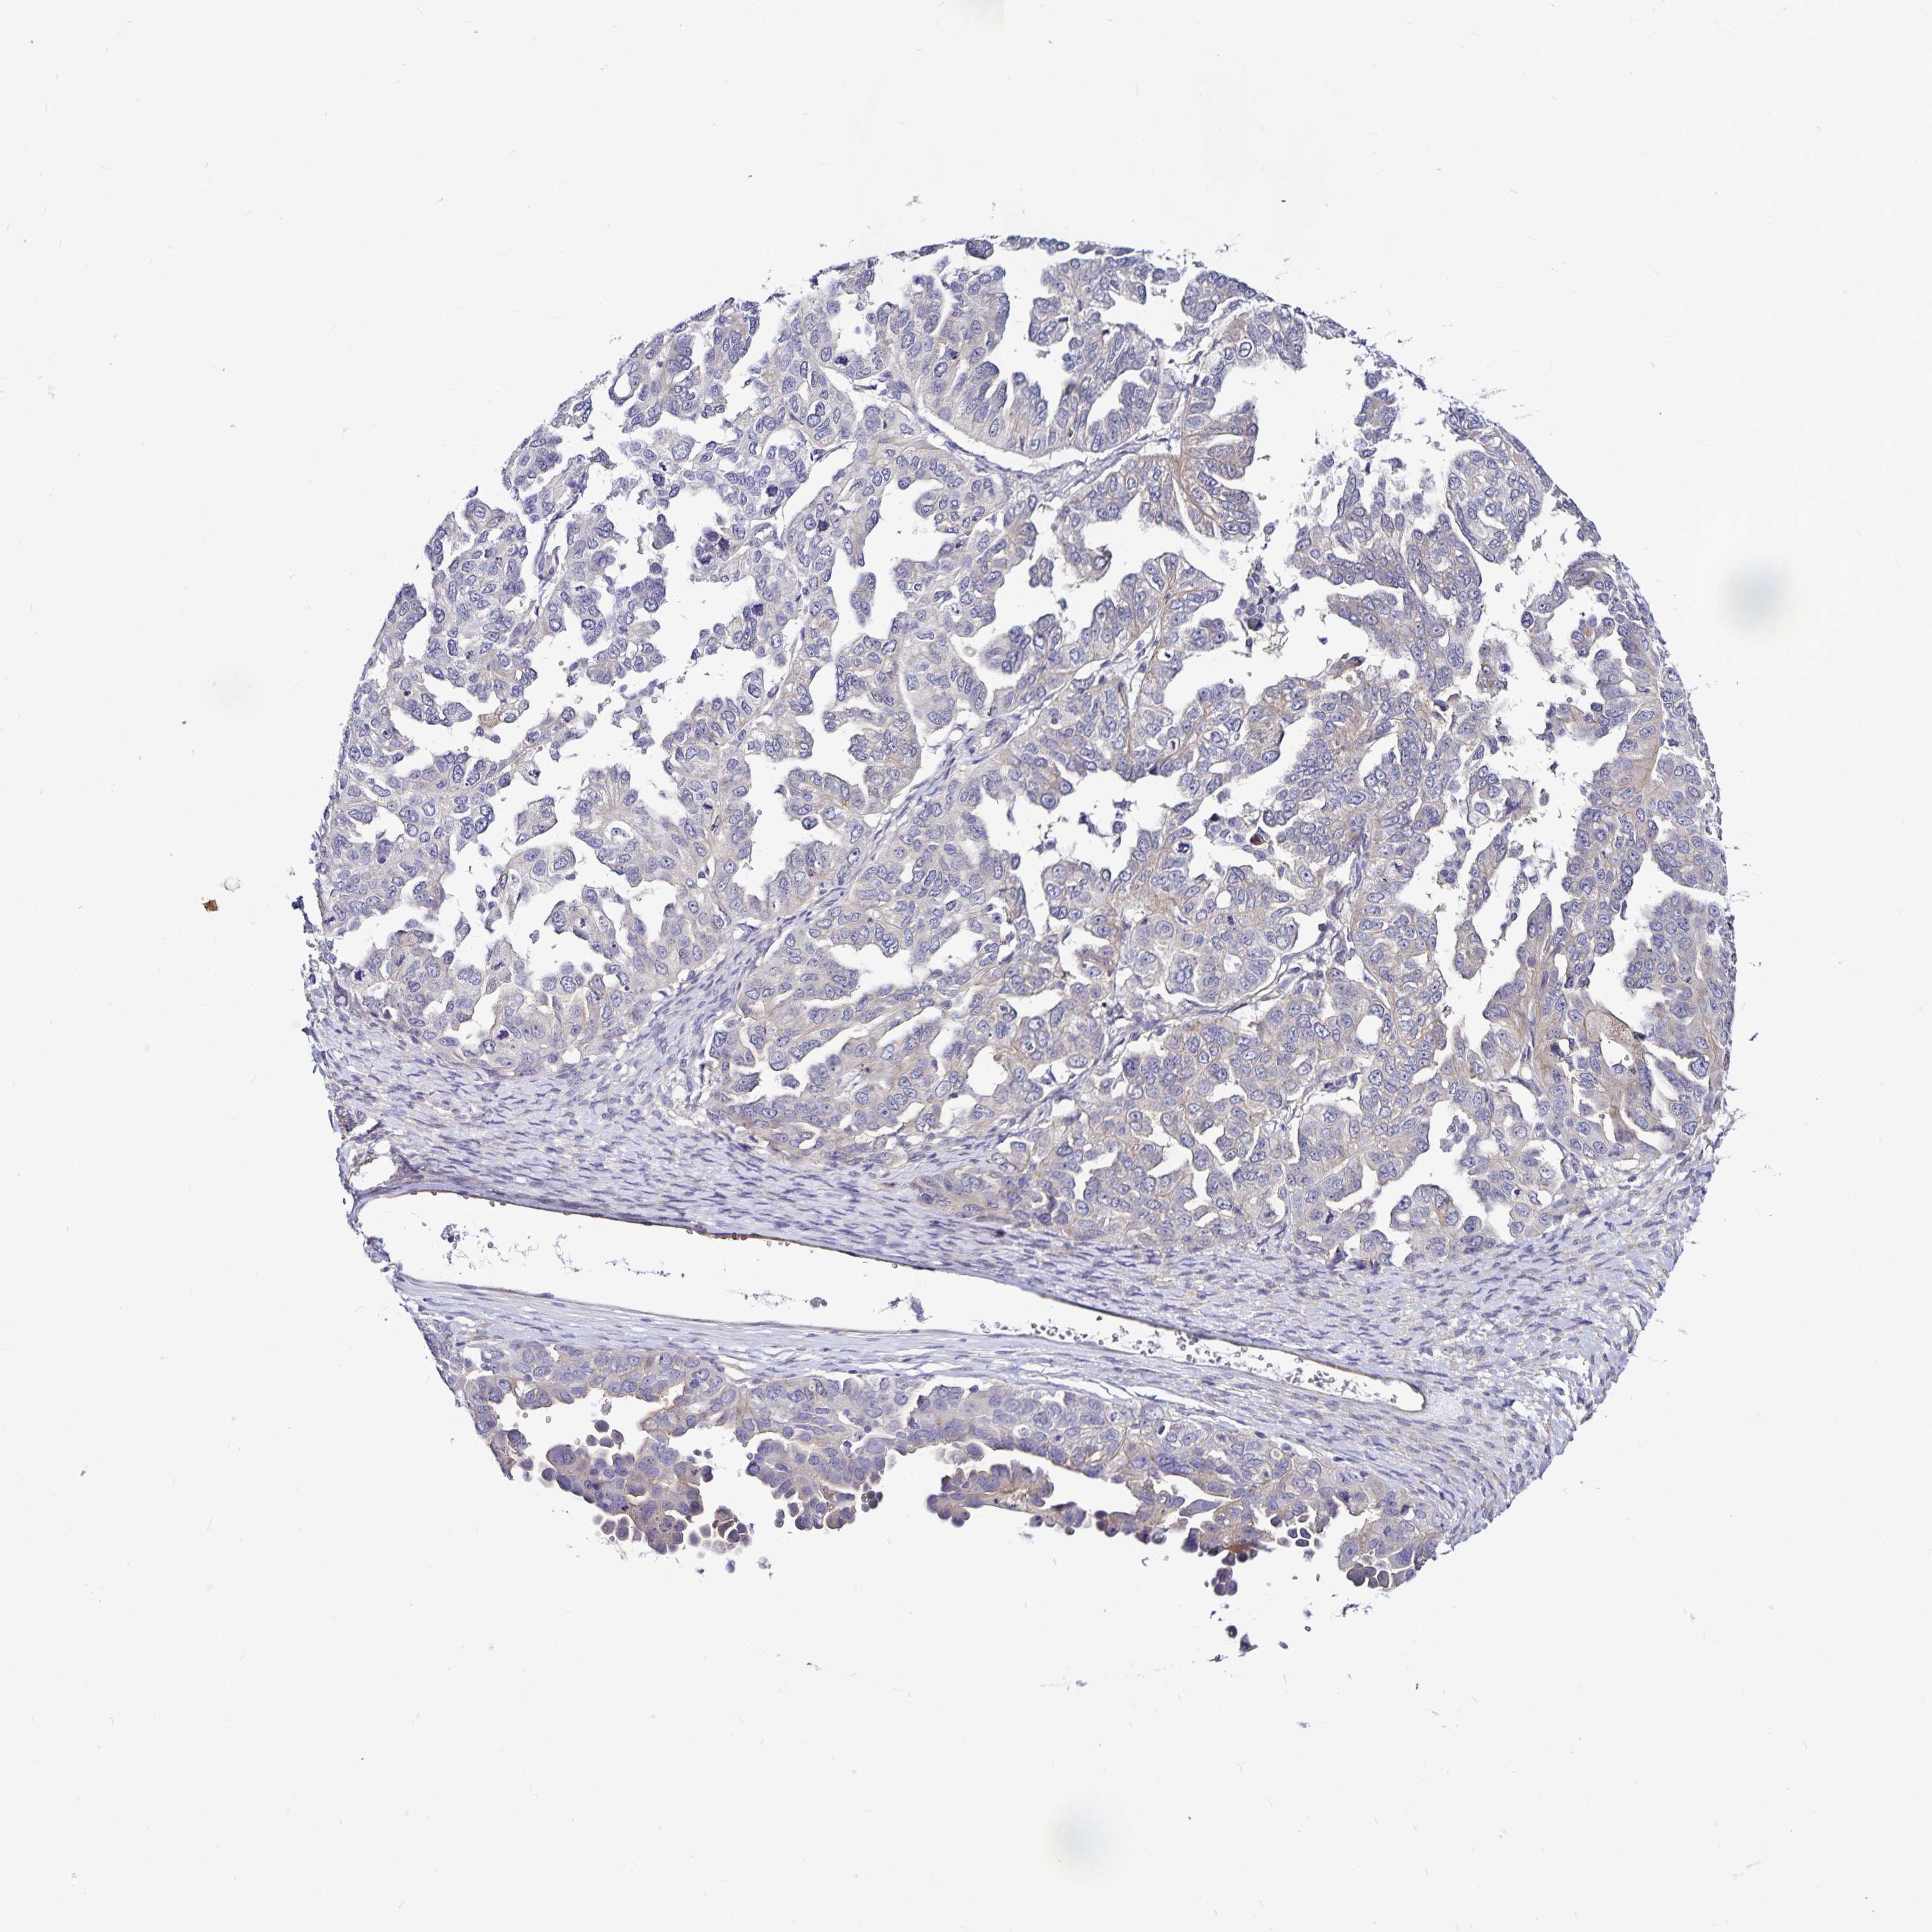

OVARIAN CANCER - Protein expressioni

A mouse-over function shows sample information and annotation data. Click on an image to view it in a full screen mode. Samples can be filtered based on level of antibody staining by selecting one or several of the following categories: high, medium, low and not detected. The assay and annotation is described here.

Note that samples used for immunohistochemistry by the Human Protein Atlas do not correspond to samples in the TCGA dataset.

Antibody stainingi

Antibody staining in the annotated cell types in the current human tissue is reported as not detected, low, medium, or high, based on conventional immunohistochemistry profiling in selected tissues. This score is based on the combination of the staining intensity and fraction of stained cells.

Each image is clickable and will lead to virtual microscopy that enables deeper exploration of all samples and also displays staining intensity scores, fraction scores and subcellular localization as well as patient and tissue information for each sample.

Antibody HPA057790

Antibody HPA062208

Staining

High

Medium

Low

Not detected

Intensity

Strong

Moderate

Weak

Negative

Quantity

>75%

75%-25%

<25%

None

Location

Nuclear

Cytoplasmic/membranous

Cytoplasmic/membranous,nuclear

Cystadenocarcinoma, serous, NOS

Cystadenocarcinoma, mucinous, NOS

Carcinoma, endometroid